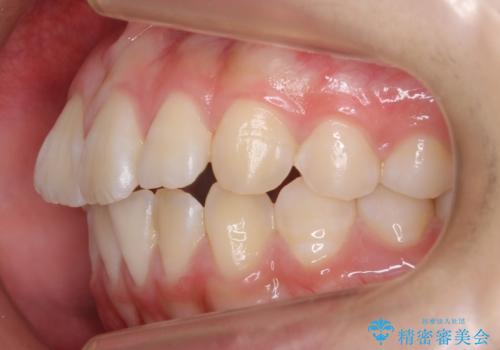

出っ歯 軽度のがたつき インビザラインで

前歯にオープンバイト気味の症状がありましたが、前歯を後ろに下げることでしっかりかませています。

前歯のずれも治り、しっかり下がりました。

前歯を下げるのに、顎間ゴムを使用していただいています。